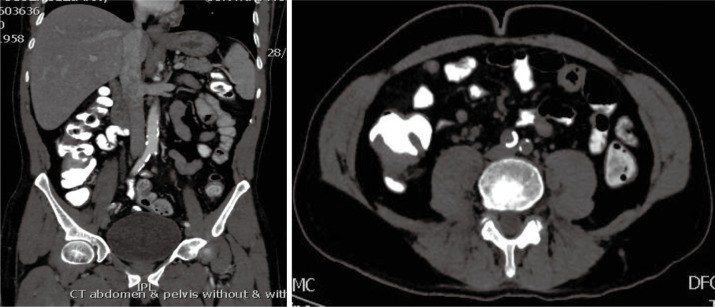

In March 2013, he presented to the American University of Beirut Medical Center (AUBMC) with 2-month history of low back pain, fevers, weight loss and mild abdominal distention. The exam showed an elderly frail man who was pale, febrile and confused. Laboratory findings were remarkable for a white cell count (WCC) of 19,200 cu/mm [normal (NL), 4,000-11,000 cu/mm], a hemoglobin (Hb) level of 9.6 g/dL (NL, 13-16 g/dL), platelets count of 272,000/mm3 (NL, 150,000-400,000/mm3); reticulocyte count of 7% (0.2-2.0%), and lactate dehydrogenase (LDH) 2,333 IU/L (NL, 200-480 IU/L) (see Table 1 for further readings). Peripheral blood smear showed moderate schistocytosis of 2% with nucleated red blood cells (nRBCs) reaching 14% and a leukoerythroblastic reaction. Subsequently, CT of chest, abdomen and pelvis (Figure 1) revealed thickened and narrowed lower rectum with no evidence of masses or lymph nodes elsewhere in the body. PET scan (Figure 2) also revealed mild increased activity in the lower rectum with diffuse abnormal activity involving the entire skeleton. A bone marrow (BM) biopsy (Figure 3) was concomitantly done and it showed more than 90% extensively necrotic malignant cells in the marrow and scattered viable hematopoietic component with cohesive clusters of large carcinomatous cells. The latter stained positive for cytokeratin 20 (CK20) and CDX-2 and negative for CK7 and PSA, suggesting a gastrointestinal origin. In view of the mentioned findings and a high serum CEA level of 566 ng/mL (NL, 0-7 ng/mL), colonoscopy followed and showed a large rectal mass (Figure 4) biopsy of which proved positive for invasive poorly differentiated adenocarcinoma. Molecular studies of the tumor revealed a wild-type KRAS gene in codons 12 and 13.

Figure 1.

Pelvic cut of the CT scan showing thickened lower rectum (red arrow).